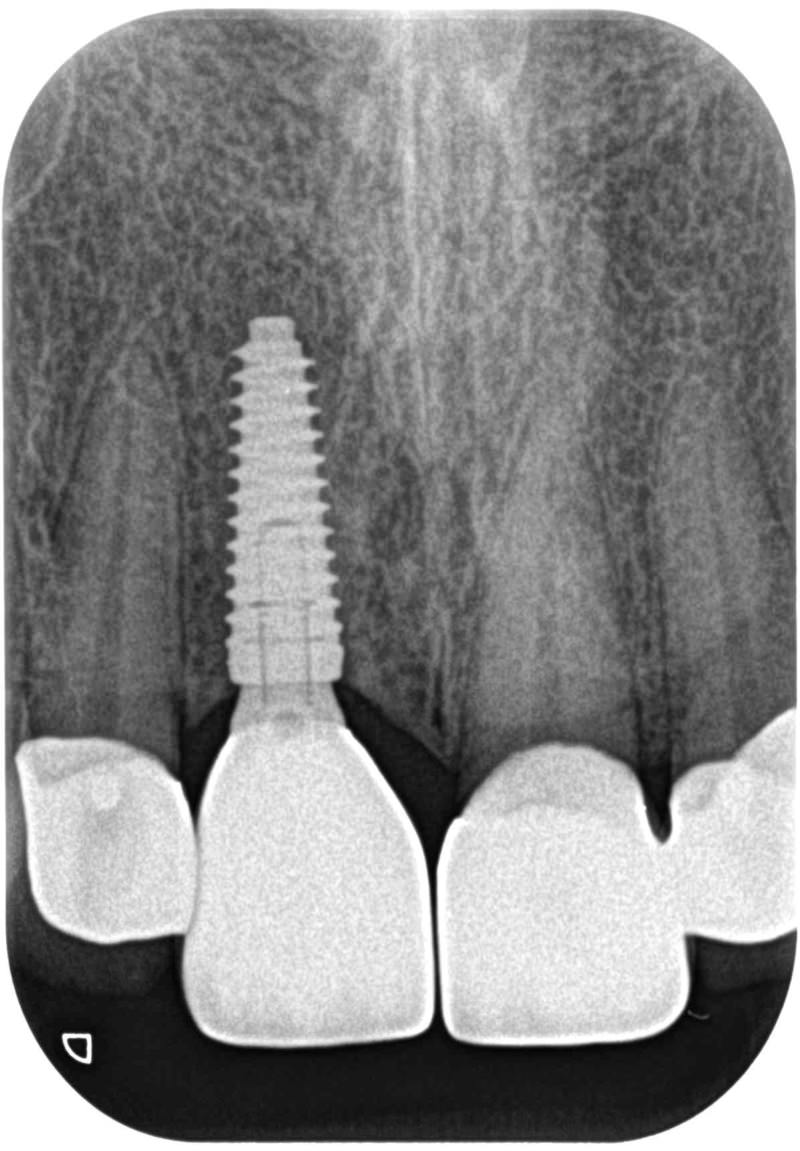

症例470歳 男性 主訴 前歯部がグラグラし、噛みにくい

治療前

治療後(3年経過)

※説明

主訴 前歯部ブリッジの動揺の為来院。歯ぎしり、喰いしばりによる力の影響である為、つなげるブリッジではなく、インプラントを選択。インプラント埋入と同時に即時荷重非接触型の仮歯を装着。

約4ヶ月後の免荷期間を経て、ジルコニアを装着。

リスクとしては、外科的侵襲がある。デメリットは、保険外診療の為、経済的負担がある。

費用 53万(税込)(オペ・仮歯・最終補綴物まで含む)